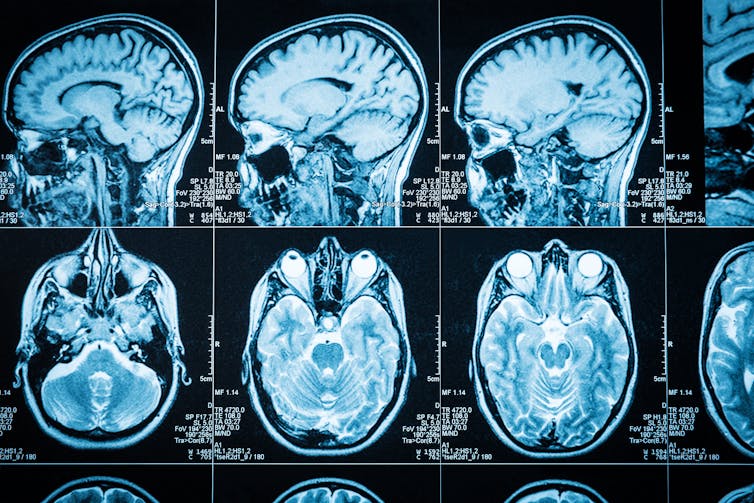

The brain needs a constant and steady supply of oxygenated blood. When it is injured – for example by an aneurysm, sudden impact against the inside of the skull, stroke or surgery – oxygen supply can be interrupted.

Sometimes, a piece is surgically removed or a region dies off due to lack of oxygen.

For example, sometimes a person with epilepsy doesn’t respond to drugs. Thanks to extraordinary brain imaging techniques, we can potentially work out the exact place in the brain the seizure is starting and remove part of the brain.

Your brain has about 100 billion neurons and over a trillion synapses (a junction between two neurons, across which an electrical impulse is transmitted). They are constantly rewiring themselves in response to new experiences, to store and retrieve information.

With brain injury, the changes can be bigger; you get certain rewiring around the injury. These synapses can rearrange themselves to work around the damaged part.

Axons (long, threadlike parts of a nerve cell that can conduct electrical impulses) form nerve fibres that get sent out to new spots in response to signals they are getting from the damaged area.